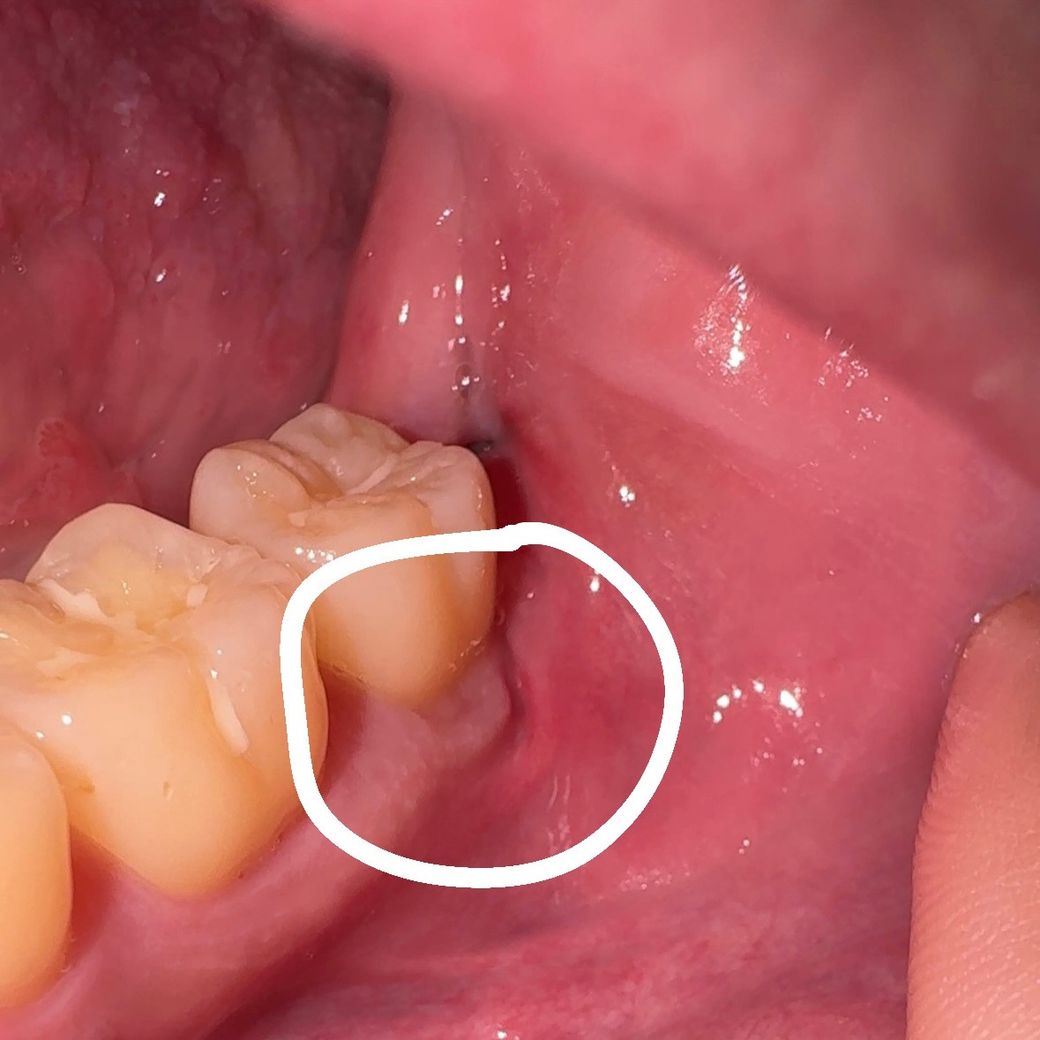

아래 매복 사랑니 발치 후 10일 정도 지났는데 저렇게 벌어지는 잇몸을 발견했습니다. 봉합을 안한걸까요? 병원에 다시 가봐야하는지 의문입니다.

아래 매복 사랑니 발치 후 10일 정도 지났는데 저렇게 벌어지는 잇몸을 발견했습니다

잇몸에 층이 나뉘어서 그렇지 잇몸이 벌어진 양상은 아닌 것으로 사진상 보입니다. 사랑니 발치 부위 잇몸 치유 과정에서 저렇게 잇몸 모양이 형성된 것 같습니다. 큰 문제는 없어 보입니다.

사랑니를 발치하고 나면 발치한 부위가 벌어지는 경우가 있습니다. 이런 증상은 대부분 시간이 지나면 없어지기 때문에 해당부위를 자극하지 않는것이 좋습니다.